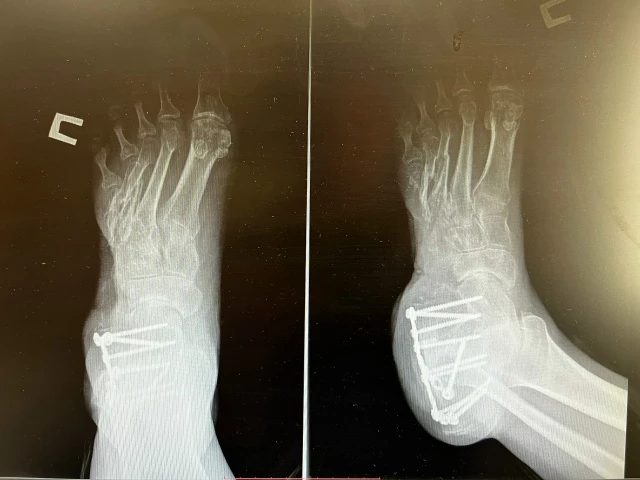

Молодому человеку грозили костыли и мучительная боль при каждом шаге. Однако хирурги отказались ставить крест на его здоровье. Пока одна бригада иссекала грубые рубцы, травматологи забрали у бойца фрагмент тазовой кости. Этот универсальный «аутодонор» размером 6,5 см в длину превратили в протез пятой плюсневой кости. Рану закрыли кожным лоскутом с голени, перемещенным вместе с питающими сосудами.

Сложнейшая реконструкция нарушенного скелета и размозженных тканей прошла успешно. Сейчас процесс заживления идет нормально, и врачи воздерживаются от прогнозов о выписке, но смотрят в будущее с оптимизмом. В перспективе пациент, который уже было смирился с ограничениями, сможет забыть о травме и вернуться к полноценным физическим нагрузкам.